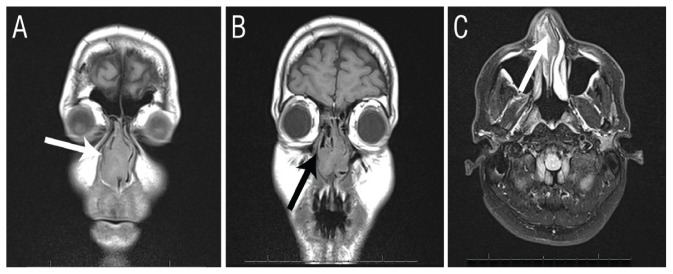

Computed tomography and magnetic resonance imaging scans of the nose and paranasal sinuses revealed a highly vascularised mass occupying the entire nasal cavity. The sinuses were intact without bony erosion or extension to the adjacent anatomical areas [Figure 1]. Under general anaesthesia, resectioning of the lower turbinate was performed and a biopsy of the mass and the involved mucosa was taken. Significant bleeding was encountered and controlled by laser vaporisation of the mucosa edges. A fresh frozen section examination of the biopsy suggested a fungal infection; however, a fungal culture did not yield any growth. The patient was therefore suspected of having aspergillosis.

Figure 1.

Imaging of a 42-year-old male patient with excessive nasal bleeding and a suspected nasal tumour. A & B: Computed tomography scans confirming the intact nasal bony wall (arrows). C: Magnetic resonance imaging showing increased T2 signals in the nasal cavity alone (arrow), without intracranial spread or extension to the sinuses.